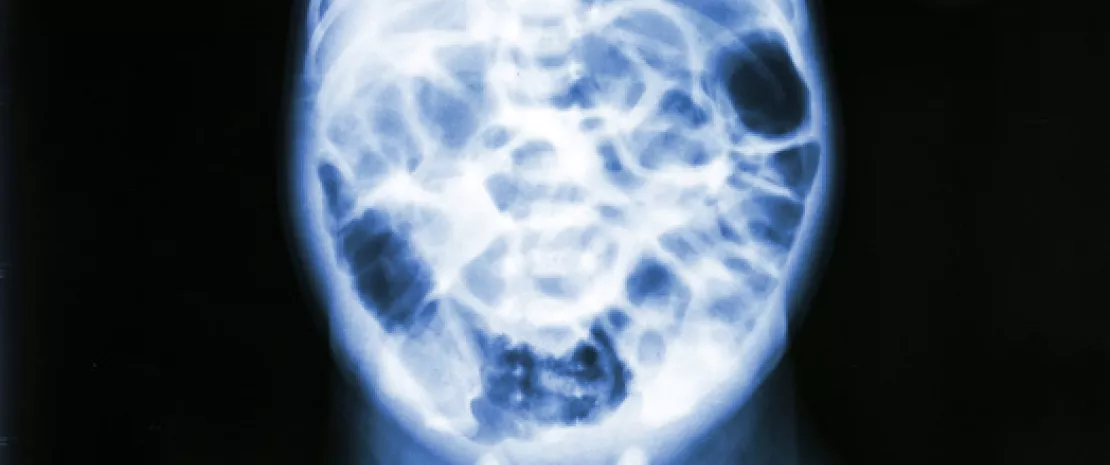

32 haftadan önce doğan prematüre bebeklerde önemli bir ölüm veya ciddi morbidite nedeni olan NEC karmaşık bir gastrointestinal hastalıktır. Hastalığın altında yatan mekanizmalar, spesifik semptom ve testlerin eksikliği nedeniyle güç olan tanısı ile birlikte hala iyi anlaşılmış değildir. Diğer yandan disialillacto-N-tetraozun (DSLNT) dahil olduğu bazı insan sütü olgosakkaritlerinin ( (sidenote: Human Milk Oligosaccharide ) ) koruyucu rolü var gibi görünmektedir. Böylece anne HMO profilleri ile bir yanda bebeğin bağırsak mikrobiyotasının gelişimi arasındaki etkileşimleri ve diğer yandan bunların NEC ile ilişkilerini değerlendiren bu çalışma ortaya çıkmıştır.